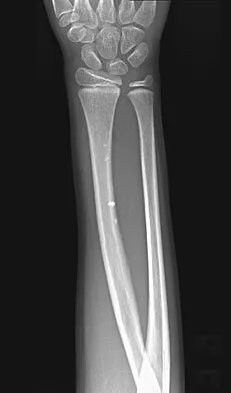

Figures 45a and 45b show the radiographs of a 14-year-old boy who sustained a distal radius fracture while playing hockey. After 1 year the patient is asymptomatic. Follow-up and comparison radiographs and an MRI scan are shown in Figures 45c and 45d. What is the next most appropriate step in management?

Explanation

The patient sustained a growth plate fracture of the distal radius and ulna. Although treated with closed reduction and casting, the follow-up radiographs demonstrate shortening of the radius in comparison to the ulna, and the MRI scan confirms thinning of the distal radius growth plate and bony bars consistent with a growth arrest. At this time, the discrepancy in length is too minor to consider lengthening of the radius; in addition, excision of a physeal bar with minimal growth potential is not likely to restore the gross discrepancy. Ulnar styloid fractures are rarely symptomatic and do not require treatment in the asymptomatic patient. Closure of the distal ulna growth plate will prevent further discrepancy between the radius and ulna. Vanheest A: Wrist deformities after fracture. Hand Clin 2006;22:113-120.